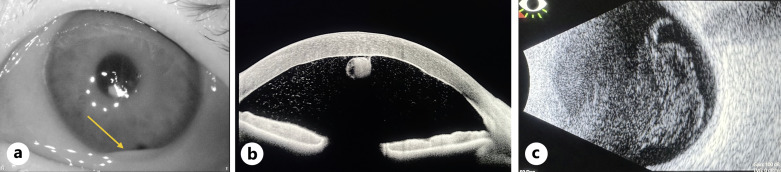

Case presentation: A 67-year-old female with a prior ocular history of bilateral cataract surgery, Fuchs endothelial dystrophy, and pseudophakic DMEK in the left eye presented with endophthalmitis 2 months after keratoplasty. DMEK graft removal without replacement with an intracameral washout, pars plana vitrectomy, intracameral, and intravitreal antibiotics resulted in an excellent visual outcome (20/25).

Conclusion: This is a unique case of late endophthalmitis following DMEK surgery requiring graft removal and pars plana vitrectomy with excellent visual recovery without donor replacement.